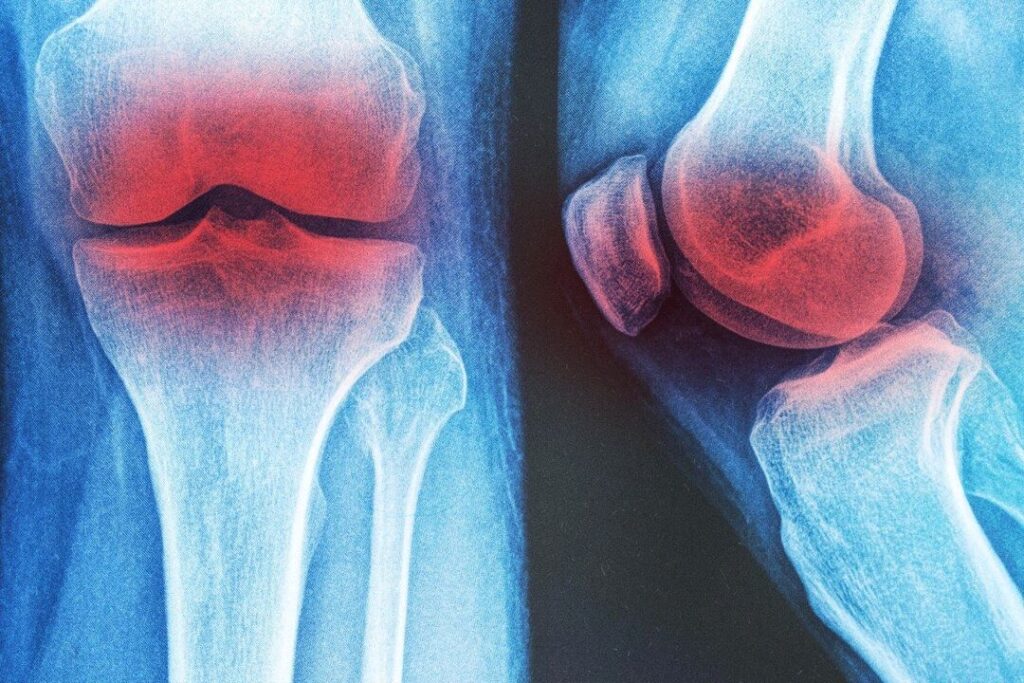

60歳以上の男性の約10%、女性の約13%が膝の変形性関節症を患っており、痛みや障害を伴う状態です。

6月に『PLOS One』に掲載されたネットワークメタ分析では、膝の変形性関節症に対する12の理学療法を比較しました。研究者は、12の療法の中で膝装具が最良の選択肢であると結論づけ、次いで水治療法(ハイドロセラピー)と一般的な運動が効果的であるとしました。

分析の結果、膝サポーターは痛みの軽減、こわばりの緩和、機能の改善において高いスコアを示し、最も有効な介入である可能性が高いとされました。水治療法は痛みの軽減に非常に効果的で、一般的な運動は痛みの軽減と機能の向上に一貫して効果的でした。体外衝撃波療法や高出力レーザー療法には一定の利点が見られましたが、超音波療法は最も効果が低い結果でした。